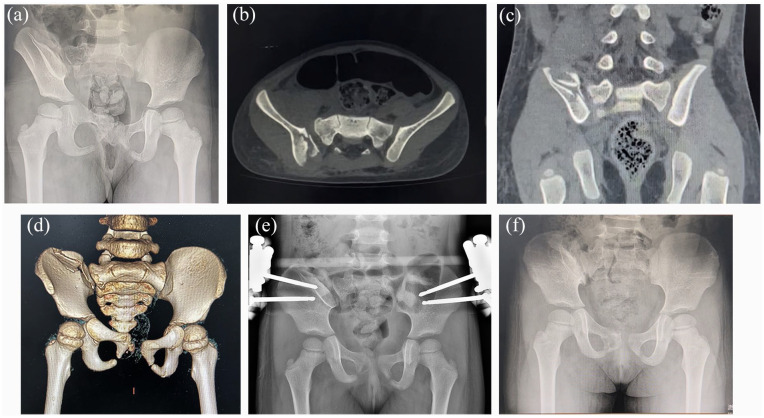

Purpose: We retrospectively analyzed the data of patients who underwent external fixation treatment for unstable pelvic fractures and evaluated the clinical effects of this treatment and factors influencing pelvic function recovery. Methods: The data of patients with unstable pelvic fractures treated with an external fixator between January 2006 and December 2018 were retrospectively analyzed. The analyzed parameters included demographic data, fracture healing, pelvic asymmetry, deformity index, and complications. Fractures were categorized using the Tiles classification. Pelvic function was evaluated using the Cole score. Pelvic risk factors were identified using univariate and multivariate logistic regression analyses. Results: Fifty-six patients (29 and 27 with type B and C fractures, respectively) were included. All fractures were healed at the time of the final follow-up. Nine and three patients had pin tract infections and loosened external fixators postoperatively, respectively. Pelvic asymmetry was reduced from 1.34 ± 0.15 cm to 0.70 ± 0.19 cm (p < 0.01), and the deformity index decreased from 0.13 ± 0.03 to 0.07 ± 0.02 (p < 0.01). The Cole score was excellent and good in 41 and 15 patients, respectively. Risk factors for pelvic function recovery included injury severity score > 25.5, age > 11.3 years, and lower-extremity fractures. Conclusions: External fixation is an effective method for treating unstable pelvic fractures in children, with the advantages of a simple operation, short surgical time, no interference with treatments for associated injuries, and avoidance of re-trauma caused by open reduction. An ISS > 25.5, patient age > 11.3 years, and associated lower-extremity fractures are predictors of pelvic function recovery. Level of evidence: Level IV.